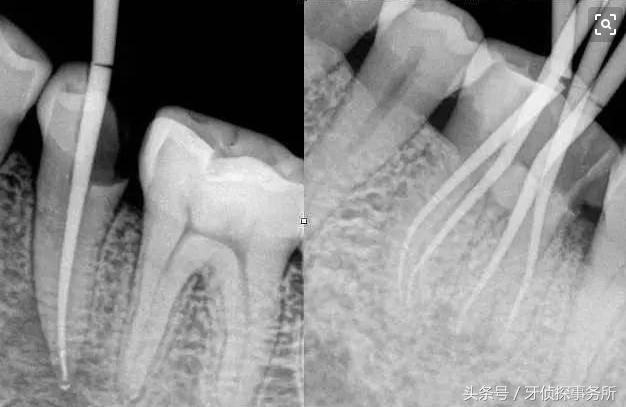

牙齿的根管治疗(杀神经)就是将自然牙(有生命力的牙齿)变成“假牙”(没有生命的牙体)的过程。而为什么要对牙齿进行根管治疗,为什么要把牙齿的神经抽掉?

因为这是一种无可奈何的“顾全大局”。当患者的牙齿因龋齿、折冠等因素引起的牙髓坏死,根尖病变,患者疼痛难忍。为以防坏死组织的进一步扩散,解除疼痛,医生一般建议患者接受根管治疗。清除髓腔内坏死组织,抽掉神经,再进行治疗填充修复,保住牙体,恢复牙齿的正常咀嚼功能。